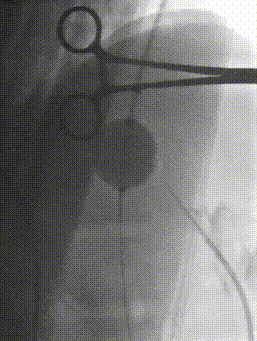

6. 经颈静脉置入抓捕器,引出泥鳅导丝,建立贯穿轨道。

7. 经肠系膜导管置入8mm球囊,扩张后将10F鞘管自下腔静脉引入门静脉远端。

8. 置入8*50mm覆膜支架建立门静脉下腔静脉分流道。造影提示:分流效果满意。